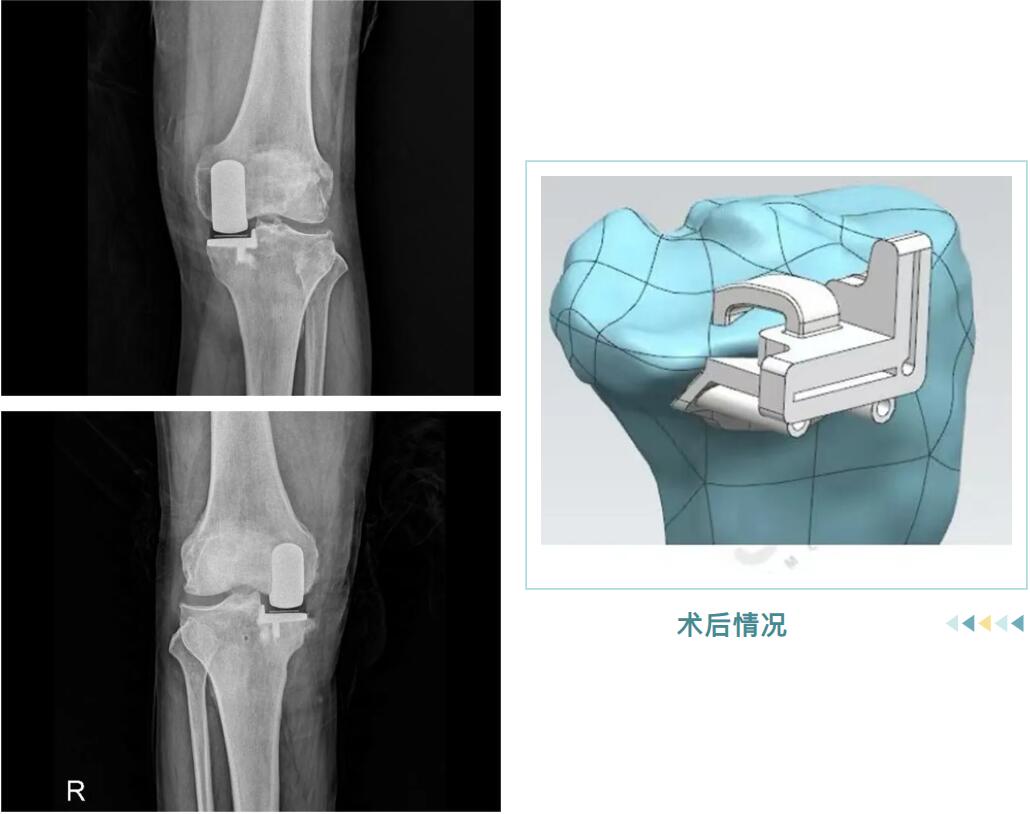

從精準(zhǔn)的3D術(shù)前規(guī)劃,到羅院長團隊嫻熟的手術(shù)操作,再到術(shù)后個性化的康復(fù)指導(dǎo),整個過程高效而順利。很快,邵阿伯的“羅圈腿”變直了,術(shù)后他輕松站起,行走時仿佛時光倒流十年。

術(shù)后情況

它并非換掉整個膝蓋,而是用仿生“小墊片”精準(zhǔn)替換掉內(nèi)側(cè)磨損的軟骨面。手術(shù)僅處理病變部分,保留了您前后交叉韌帶和健康的軟骨,最大程度維持了膝關(guān)節(jié)原有的自然運動感和穩(wěn)定性。